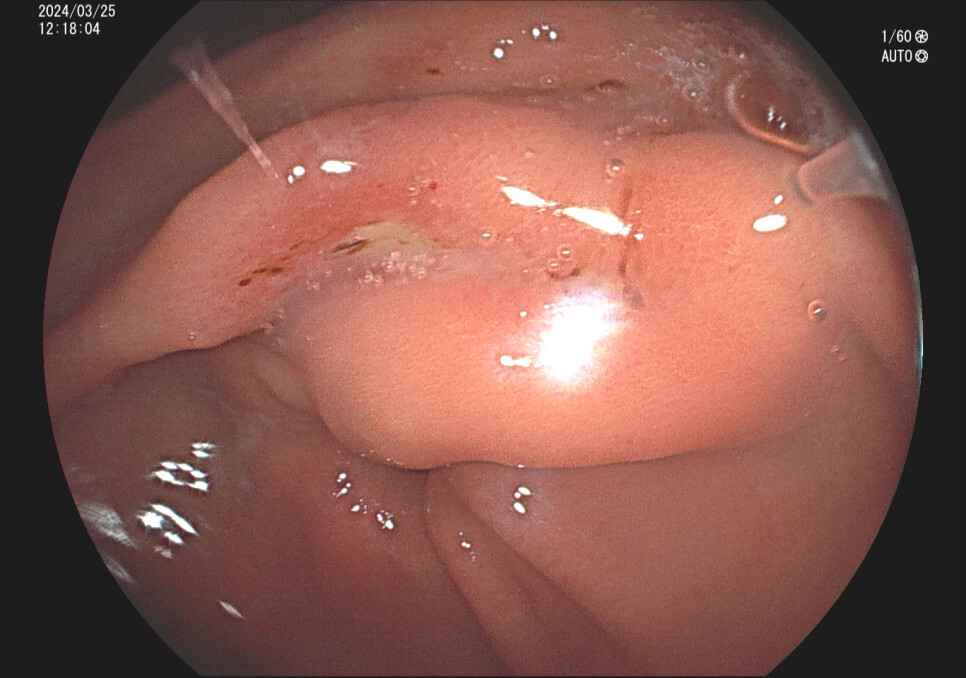

사례2. 36세 남성, 식후 속쓰림 증상으로 내원

과거 위내시경상 위궤양 의심 소견있었으나 치료 안하고 방치, 헬리코박터위염 확인됨.